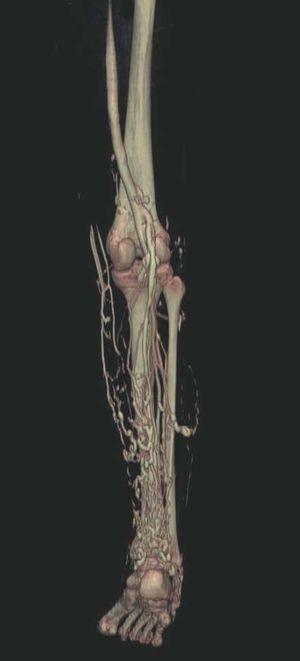

Hoy en día la utilización de los nuevos equipos TC multicorona y RM permiten la adquisición de imágenes con gran rapidez, pudiendo realizar reconstrucciones multiplanares de gran calidad, así como estudios angiográficos no invasivos13,23. Recientemente hemos estudiado 16 pacientes con síndrome de Klippel-Trenaunay mediante una venografía tomografía computarizada multicorte (TCM) o una venografía resonancia magnética tridimensional (RM-3D), utilizando imágenes axiales convencionales, reconstrucciones multiplanares (RMP), proyecciones de máxima intensidad (PMI) e imágenes tridimensionales (figs. 1-3). Las imágenes axiales convencionales fueron de utilidad para evaluar el tejido blando y el hueso y permitieron localizar el sistema venoso profundo y los vasos anómalos superficiales, determinando su relación con estructuras adyacentes. Las imágenes axiales, RMP y PMI fueron empleadas para trazar el origen, trayecto y extensión de las malformaciones venosas. Las imágenes de la superficie cutánea permitieron evaluar la localización y la extensión de la mancha en vino de Oporto y demostrar la hipertrofia de la extremidad. Las reconstrucciones tridimensionales permitieron demostrar las varicosidades y el origen y trayectoria de los vasos aberrantes (figs. 4 y 5). Ninguno de los pacientes requirió otra técnica complementaria invasiva (flebografía convencional) para confirmar el diagnóstico y planificar las estrategia terapéutica24.

Figura 4. Agenesia de la vena poplítea en paciente con síndrome de Klippel-Trenaunay.

Figura 5. Hipertrofia músculo-esquelética e hipoplasia de vena femoral superficial en paciente con síndrome de Klippel-Trenaunay.

Así, podemos concluir que una venografía TC o una venografía RM en 3D en niños y embarazadas para limitar la radiación puede ser la prueba de elección para estudiar a fondo una malformación vascular extensa localizada en una extremidad. Esta técnica permite conocer la localización exacta de la lesión en un plano tridimensional, detectando una posible infiltración musculoesquelética y extensión torácica y/o abdominopélvica, además permite valorar cambios en la densidad ósea (osteoporosis) y dismetrías, así como comprobar la existencia de sistema venoso profundo y su permeabilidad (figs. 6-9). También son de utilidad para detectar anormalidades del sistema venoso superficial, demostrar las presencia de venas aberrantes o ciáticas y determinar su extensión y vía de drenaje. Aunque estos procedimientos siguen siendo inferiores a la arteriografía o flebografía convencionales al no proporcionar el mismo grado de información sobre la hemodinámica de la malformación, representan un avance muy significativo, y en nuestra experiencia sólo será necesaria la complementación con procedimientos invasivos en casos de hipoplasias vasculares donde no esté claro el funcionamiento hemodinámico del vaso24,25.

Figura 7. La angio-tomografía axial computarizada (TAC) muestra tridimensionalmente la relación de los vasos con el tejido muscular.

Figura 8. Tras sustracción de tejidos blandos en la angio-tomografía axial computarizada (TAC) destacan venas anómalas en región gemelar y tobillo sobre plano óseo (vista lateral).

Figura 9. Detalle de la figura anterior (vista posterior).